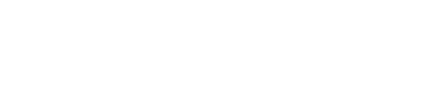

Neste ensaio clínico randomizado, 30 olhos de 30 pacientes submetidos à cirurgia de pterígio foram divididos em um Grupo de Técnica de Dissecção de Moscovici e um Grupo de Dissecção Manual. Os pacientes foram tratados e avaliados no Hospital Oftalmológico Visão Laser (Santos, São Paulo, Brasil). A tomografia de coerência óptica foi realizada para medir a espessura do enxerto 3 meses após a cirurgia. Três imagens foram obtidas de cada olho, e três medidas foram realizadas a uma distância de 1,5mm perpendicular ao limbo em cada captura. O cirurgião classificou a dificuldade de obtenção do enxerto com a técnica realizada de um (menor dificuldade) para quatro (maior dificuldade).

Encontramos diferenças estatisticamente significantes entre a dificuldade das duas técnicas e a espessura média do autoenxerto conjuntival nos dois grupos (p=0,01 e p=0,05, respectivamente). A classificação média de dificuldade para o Grupo de Técnica de Dissecção de Moscovici foi de 1,47, enquanto a do Grupo de Dissecção Manual foi de 2,20. A espessura média das três medidas foi de 252μ no Grupo de Técnica de Dissecção de Moscovici e de 298μ no Grupo de Dissecção Manual, com medianas de 250μ e 278μ, respectivamente.